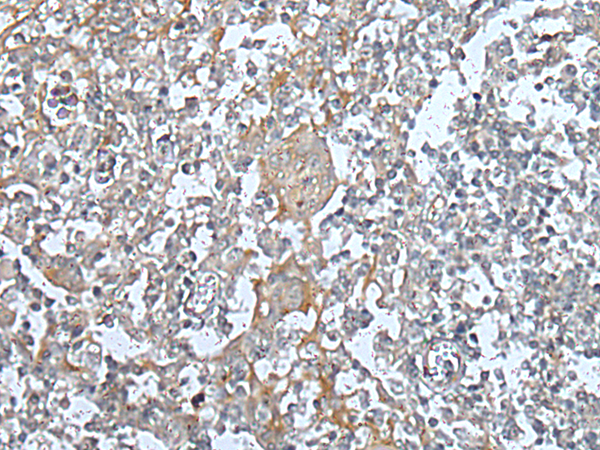

分类: 科研抗体货号: P05996别名: WAP2; SWAM2; C20orf122; dJ211D12.4应用: IHC反应种属: Human